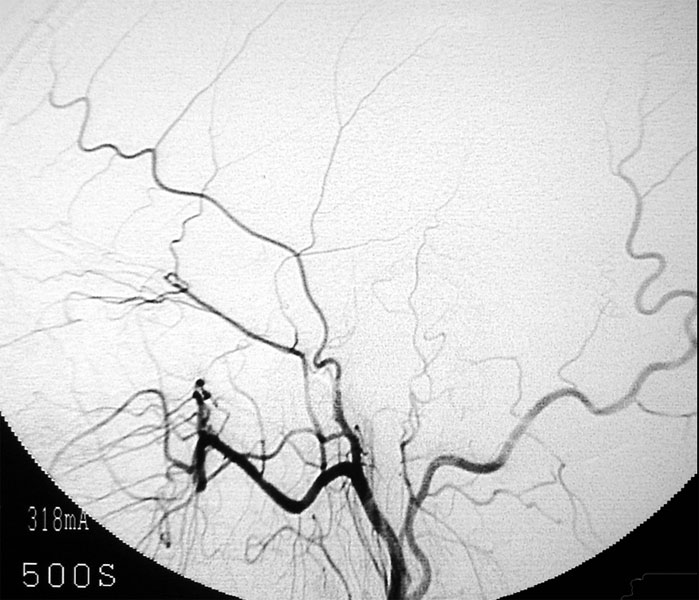

さて当科では脳梗塞予防手術を積極的に行っています。最近食生活の欧米化で内頚動脈起始部狭窄症が増加しています。この病気に対しては外科的治療と血管内治療がありますが、当科では主に外科的治療によって内頚動脈の厚くなった内膜を剥離して血管を広げ、脳梗塞を予防しています(図9、10)。

すでに詰まってしまっている患者さんに対しては症状が軽い場合であれば、頭蓋内血管と頭蓋外血管とのバイパス手術を行い、症状の悪化を予防しています(図11,図12,図13)。